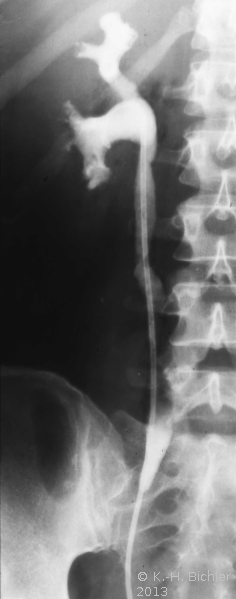

- Abbildung Harnleiterkarzinom (Urothel) links Mitte:

- c) Resektionspräparat: Harnleiterstück mit Urothelkarzinom